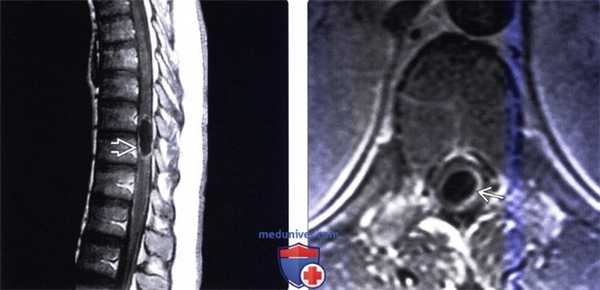

(Слева) Аксиальная КТ-миелограмма: гиподенсный интрадуральный дефект наполнения, представляющий собой цистицеркоидную кисту. Киста оттесняет собой корешки конского хвоста.

(Справа) Фронтальный срез, Т2-ВИ: фокальное кистозное образование № дистальной части грудного отдела спинного мозга, сопровождающееся его веретеновидным утолщением. Сама киста характеризуется гиперинтенсивностью сигнала, проксимальней и дистальней кисты отмечаются признаки отека паренхимы спинного мозга. Дифференциальный диагноз при подобной картине должен в первую очередь проводиться с интрамедуллярной опухолью спинного мозга.